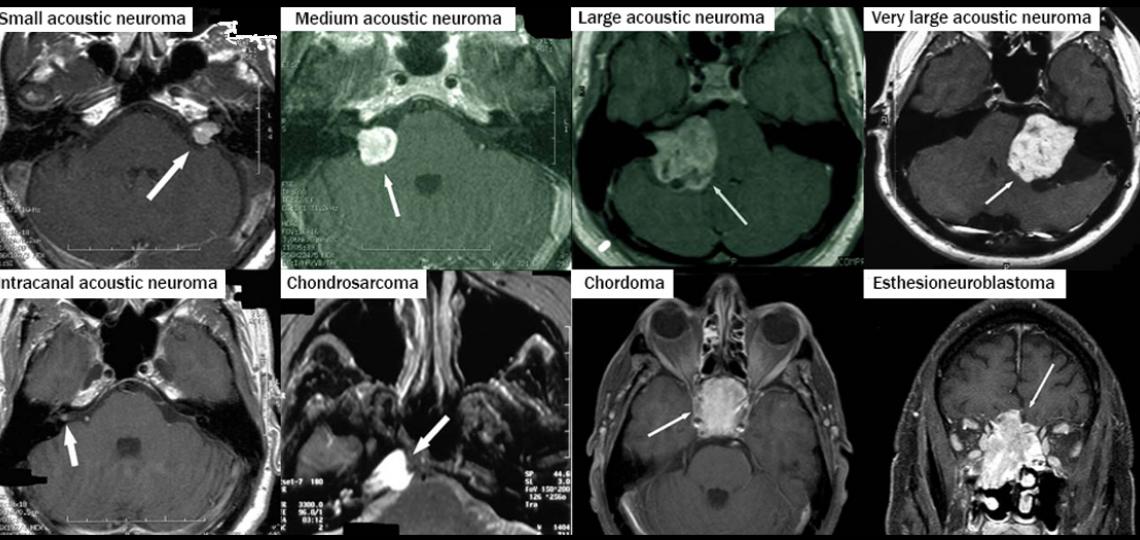

- Vestibular schwannoma/acoustic neuroma

- Chondrosarcoma